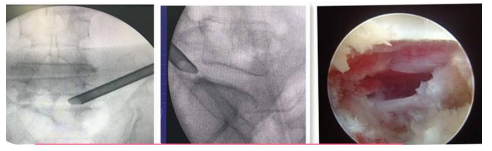

UBE(Unilateral Biportal Endscopic,單側雙通道內鏡技術):

UBE(Unilateral Biportal Endscopic,單側雙通道內鏡技術)是新興的一種脊柱外科微創技術,被廣泛應用于脊柱退行性疾病(包括腰椎間盤突出癥、腰椎滑脫、腰椎管狹窄、頸椎病等)的治療,收到了較好的臨床效果。UBE手術具有視野清晰、創傷小、出血少、效率高、療效好及恢復快的特點。我院在重慶市較早開展此項技術,多次通過手術直播、學術講座和實操培訓等形式充分展示此項技術。

椎間孔鏡技術:

利用椎間孔鏡從患者腰椎側方或者后方進入達到椎間盤突出或者其他病變部位,用專用工具將突出(脫出)的椎間盤組織或病變取出(去除)從而達到治療椎間盤突出或者椎管狹窄的目的。它的優勢在于:局部麻醉、微創、切口小(僅約7mm),出血少,恢復快(第二天即可佩戴硬腰圍下地)及療效好。